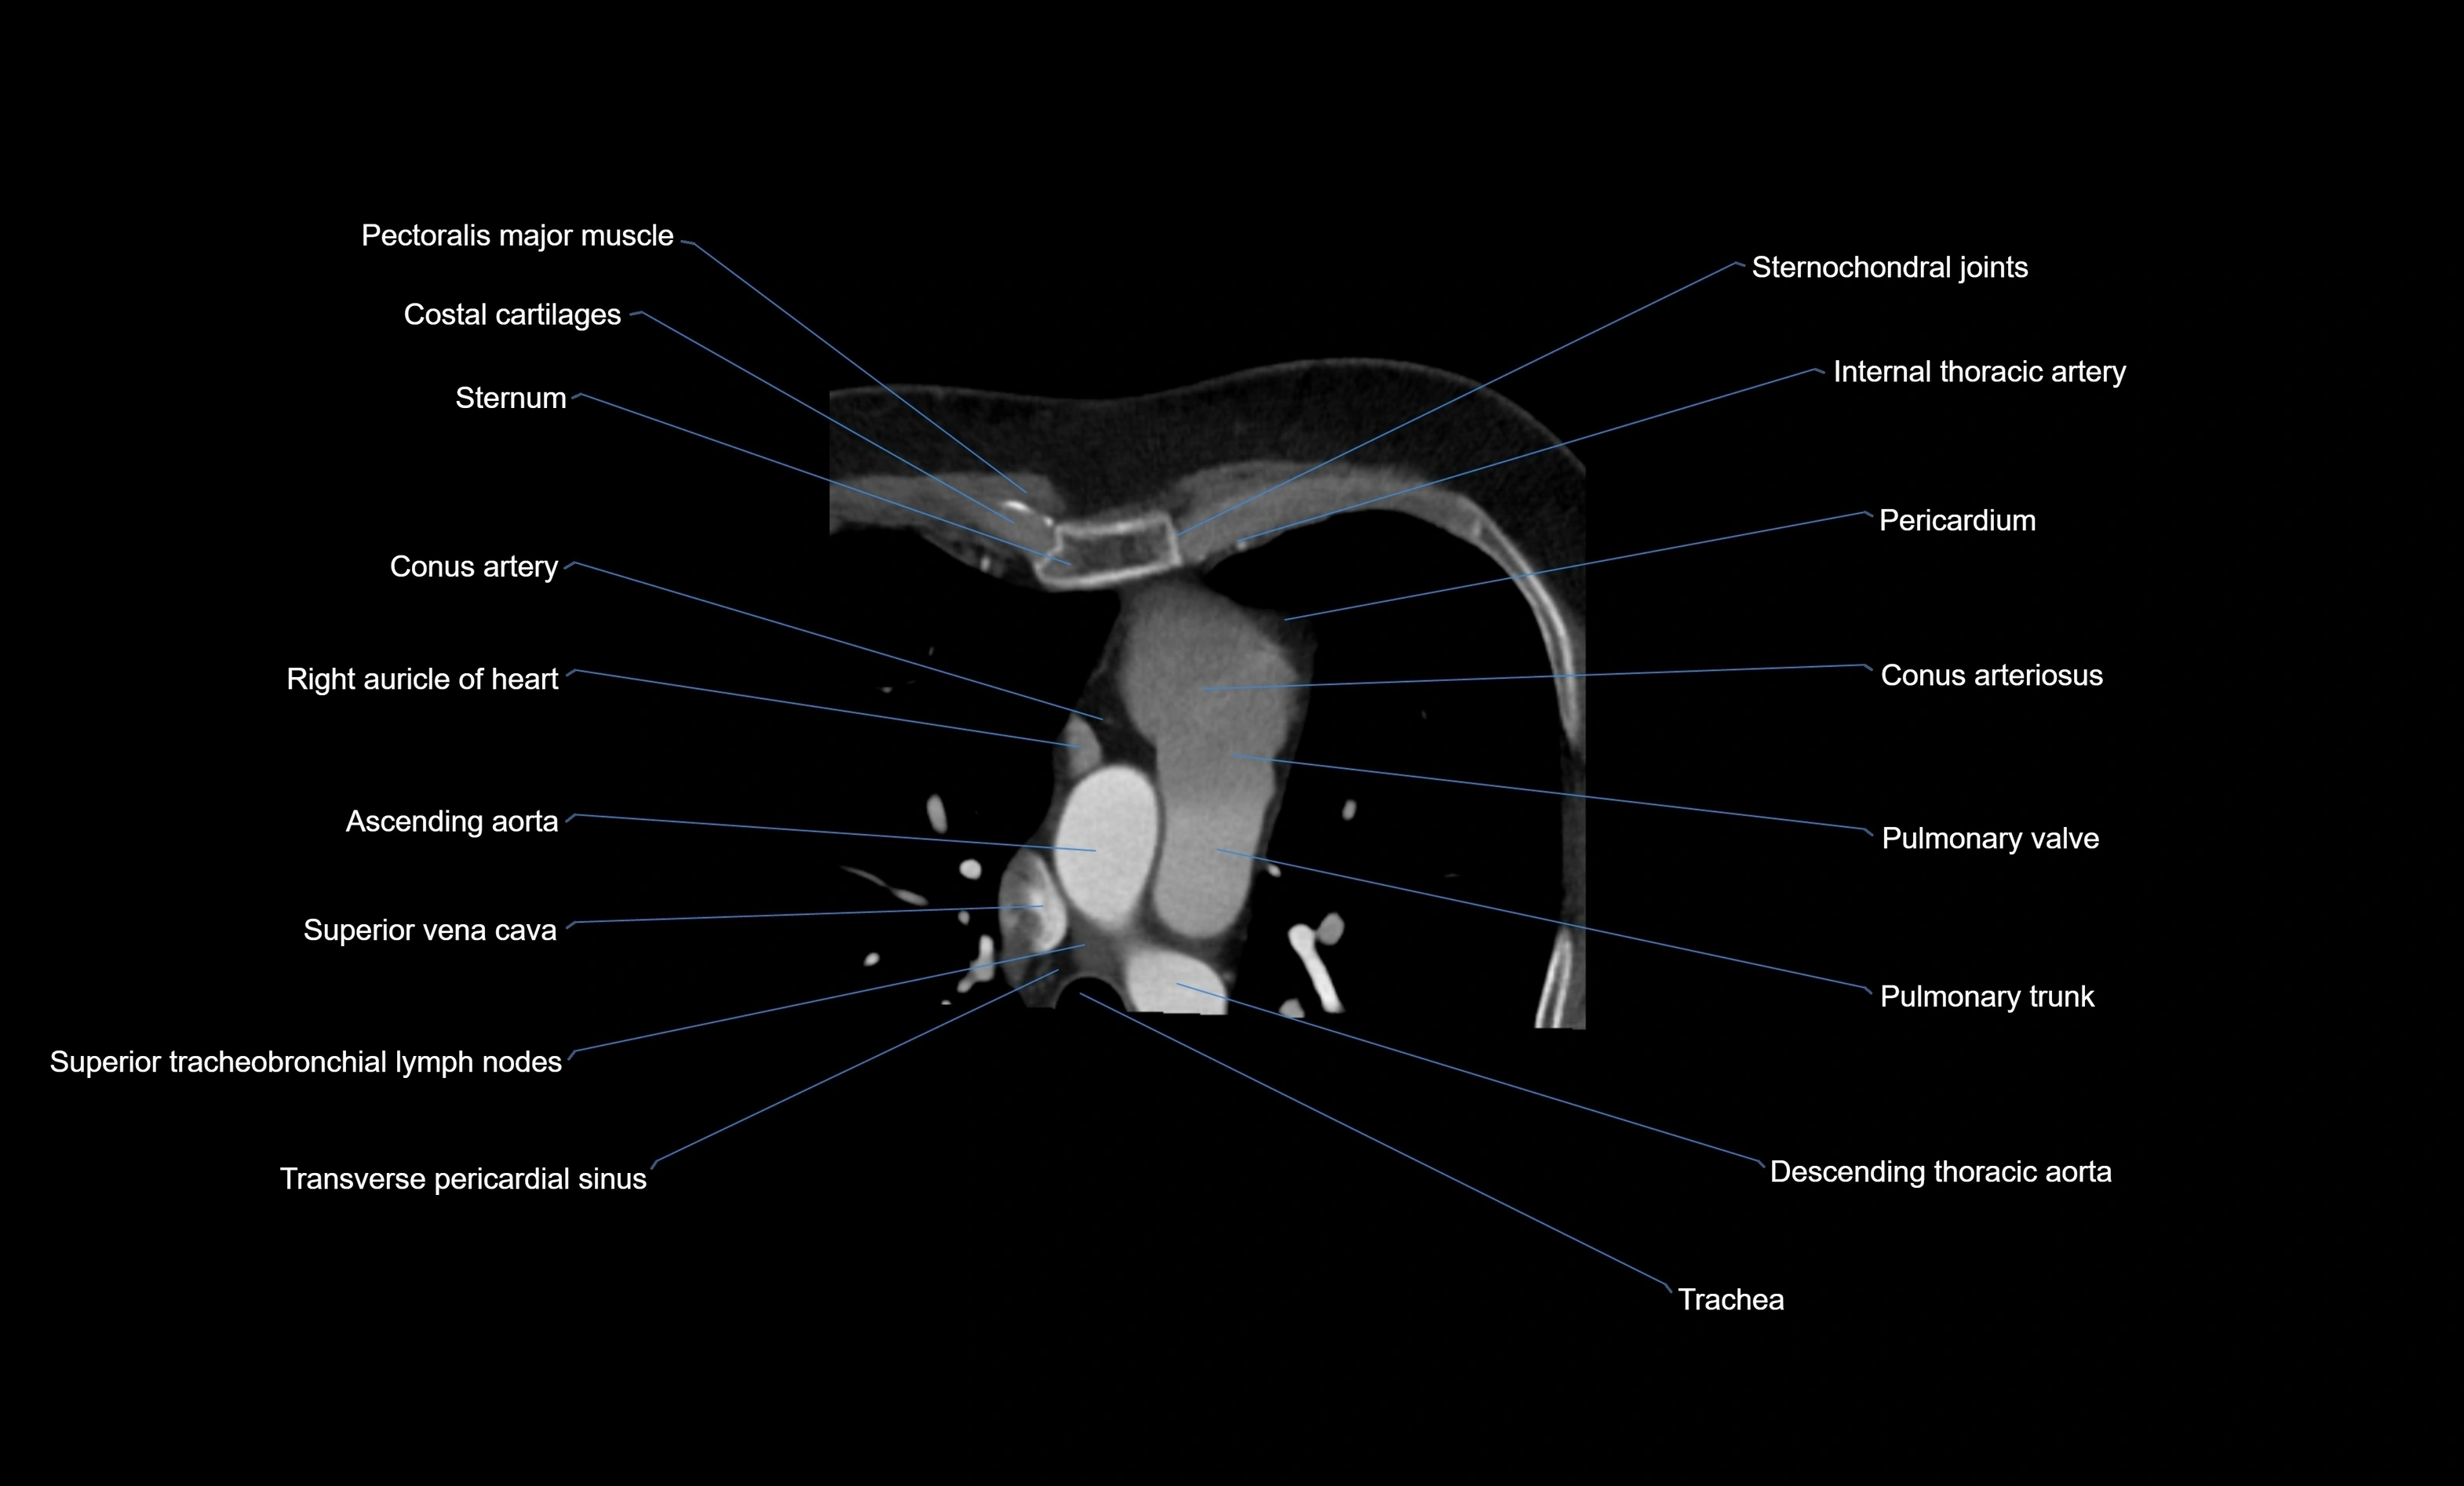

- Conus arteriosus

- Conus artery

- Pulmonary trunk

- Pulmonary valve

- Right auricle of heart

- Superior tracheobronchial lymph nodes

- Superior vena cava

- Transverse pericardial sinus

- Ascending aorta